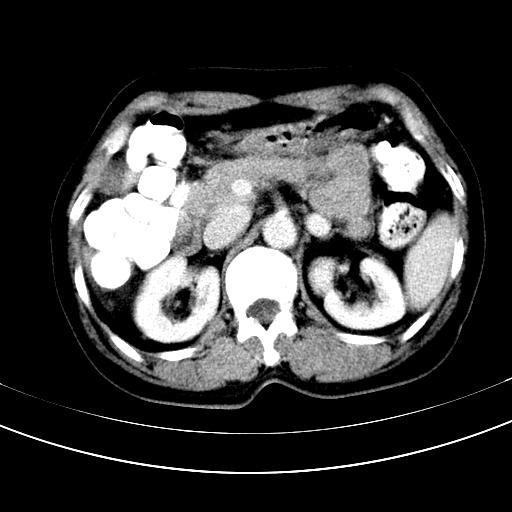

补充强化片

肝左叶及尾叶低密度灶,增强有渐进性明显强化,考虑血管瘤。胃内“充缺”首先要排除异物(食物),变换体位可鉴别。增强时机抓的不好,还应该有延时像。

谢谢楼主的增强片子,平扫没发现左侧肾上腺的问题很不好意思,可惜片子只有门脉期,所以还只有猜,肝脏的病灶在门脉期部分强化,首先考虑为血管瘤(其他的用一种病不好解释)胃要喝水就好了现在不好说是否有问题,左肾上腺的问题考虑是肿瘤。

做了增强后,可以明确胃是没有肿瘤的,肾上腺也没有肿瘤.肝左叶的病灶首先考虑血管瘤,应该再延迟,肝尾状叶的病灶仍不能排除肝癌的可能性.